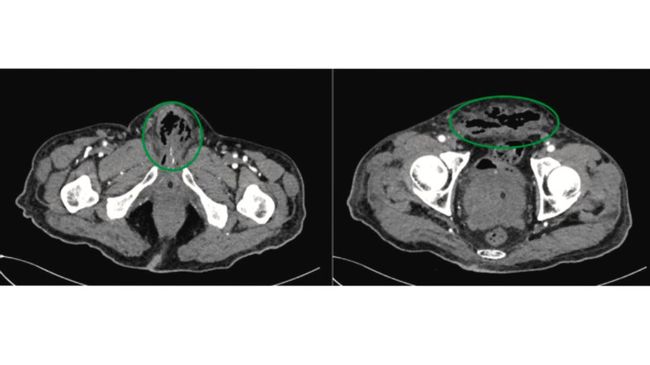

Foto: Urology Case Reports

Tetapi, pada kunjungan kedua ke rumah sakit kondisi pria itu semakin parah. Dokter harus mengamputasi penisnya karena jaringan yang ada di dalamnya menghitam akibat gangren akibat nekrosis penis total.

"Perkembangan gangren iskemik lokal pada penis merupakan kejadian yang sangat langka. Sebab, pasokan darah organ tersebut melimpah dan memiliki morbiditas dan mortalitas yang tinggi karena risiko sepsis yang tinggi," tulis para dokter yang dipublikasikan di Urology Case Reports.

"Dalam kasus ini, presentasi gangren iskemik penis dikaitkan dengan kombinasi beberapa faktor, yakni gangren Fournier sekunder akibat pemasangan kateter transuretral traumatis, diabetes melitus yang tidak terkontrol, dan penyakit arteri perifer. Penektomi total dilakukan karena kurangnya jaringan yang layak untuk penektomi parsial atau rekonstruksi," jelas para dokter.